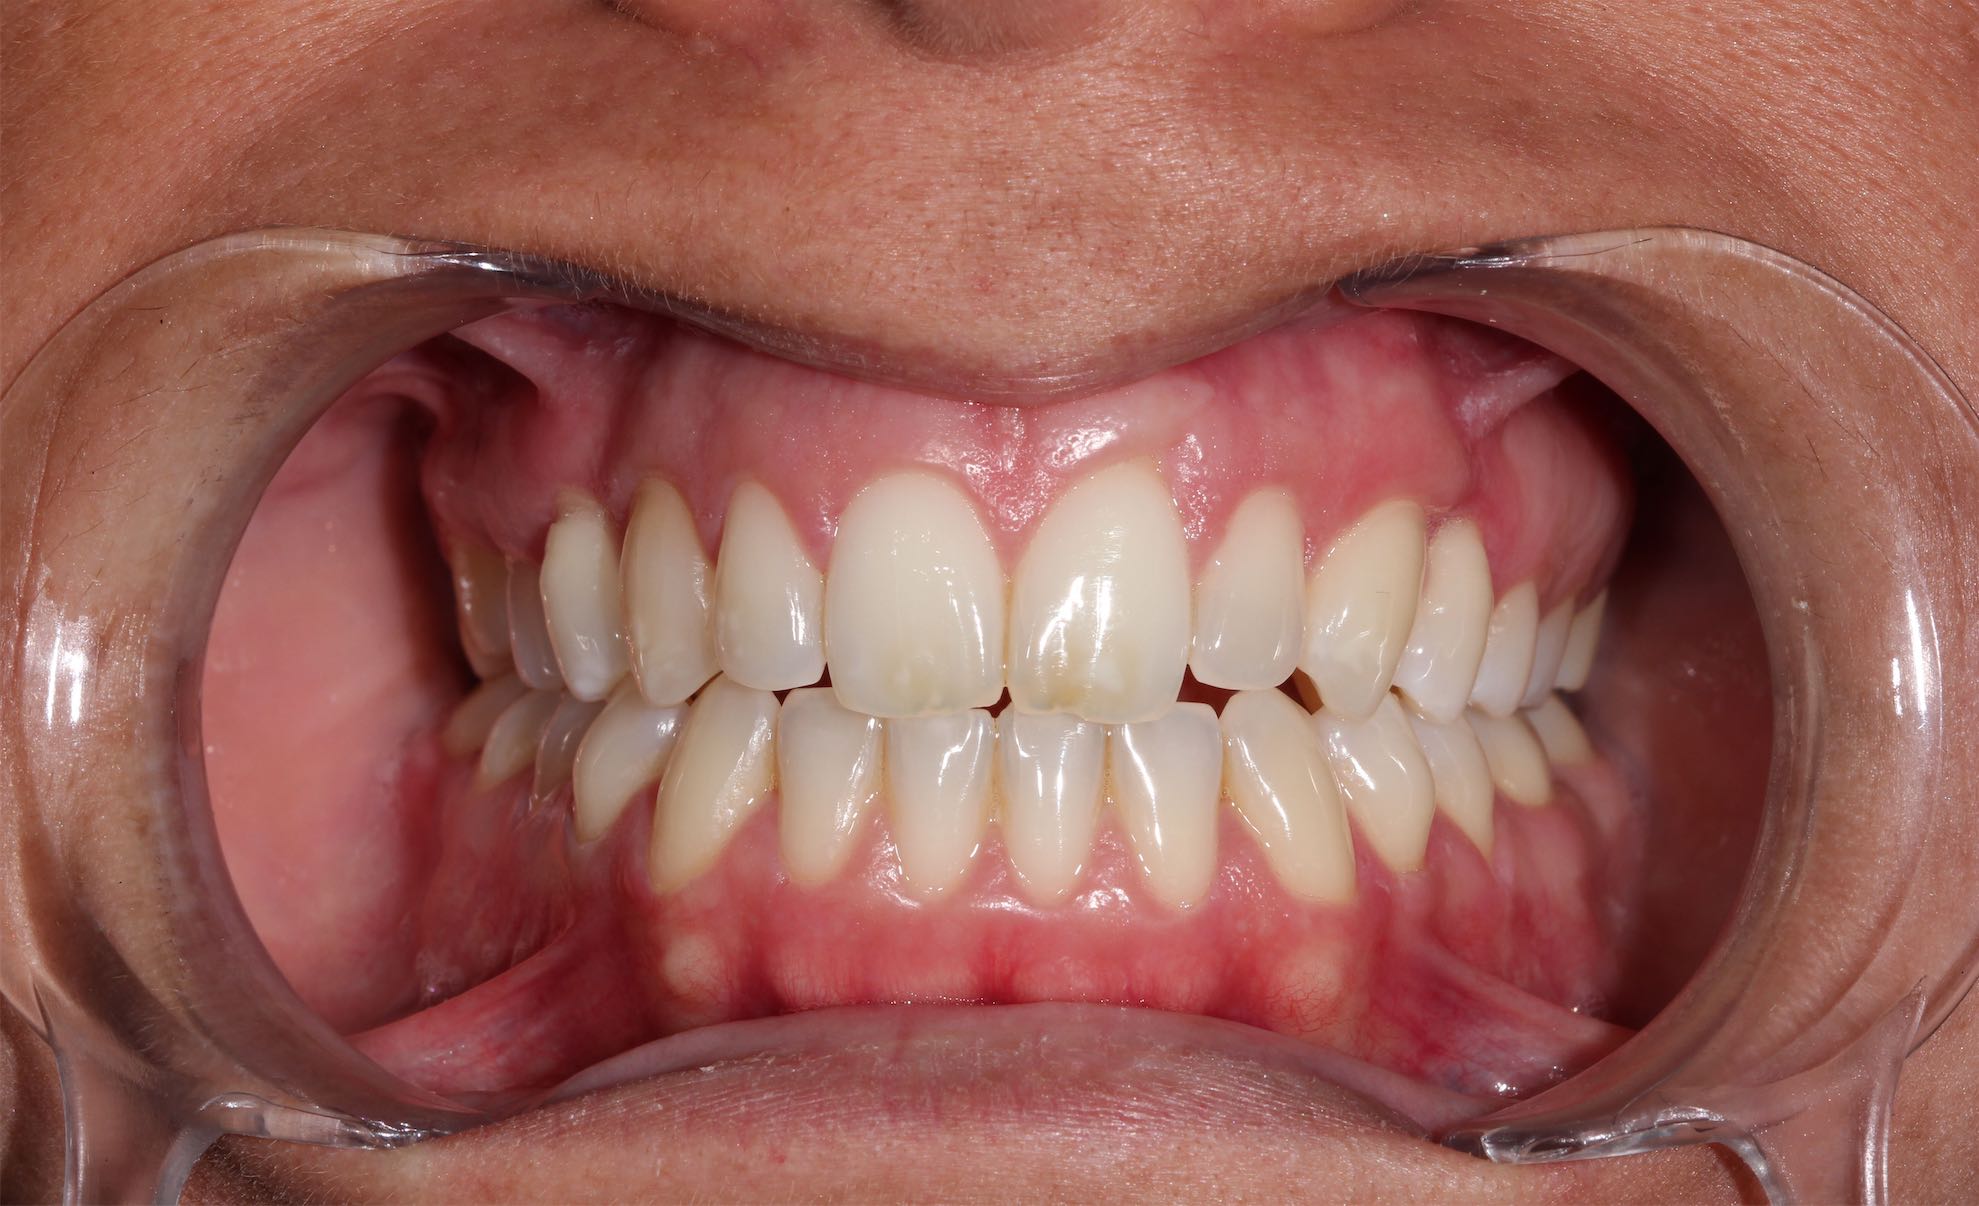

Ortodoncia

BeforeAfter